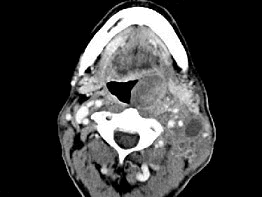

男,67岁,口咽部异物感约8个月,伴口咽部疼痛,患者无明显发热。如图所示最可能的诊断为()

男,67岁,口咽部异物感约8个月,伴口咽部疼痛,患者无明显发热,影像检查如图,最可能的诊断是<img border="0" style="width: 294px;

[单选题]男,67岁,口咽部异物感约8个月,伴口咽部疼痛,患者无明显发热,影像检查如图,最可能的诊断是A.扁桃体结核伴淋巴结转移B.扁桃体脓肿伴淋巴结转移C.扁

男,67岁,口咽部异物感约8个月,伴口咽部疼痛,患者无明显发热,影像检查如图,最可能的诊断是<img border="0" style="width: 297px;

[单选题]男,67岁,口咽部异物感约8个月,伴口咽部疼痛,患者无明显发热,影像检查如图,最可能的诊断是A.扁桃体结核伴淋巴结转移B.扁桃体脓肿伴淋巴结转移C.扁

男,67岁,口咽部异物感约8个月,伴口咽部疼痛,患者无明显发热,影像检查如图,最可能的诊断是()<img border="0" style="width: 224p

[单选题]男,67岁,口咽部异物感约8个月,伴口咽部疼痛,患者无明显发热,影像检查如图,最可能的诊断是()A.扁桃体结核伴淋巴结转移B.扁桃体脓肿伴淋巴结转移C

男,67岁,口咽部异物感约8个月,伴口咽部疼痛,患者无明显发热,影像检查如图,最可能的诊断是( )。<br /><img border="0" style=&q

[单选题]男,67岁,口咽部异物感约8个月,伴口咽部疼痛,患者无明显发热,影像检查如图,最可能的诊断是( )。A.扁桃体结核伴淋巴结转移B.扁桃体脓肿伴淋巴结

男,67岁,口咽部异物感约8个月,伴口咽部疼痛,患者无明显发热。如图所示最可能的

[单选题,A1型题] 男,67岁,口咽部异物感约8个月,伴口咽部疼痛,患者无明显发热。如图所示最可能的诊断为()A . 扁桃体结核伴淋巴结转移B . 扁桃体脓肿伴淋巴结转移C . 扁桃体癌伴淋巴结转移D . 扁桃体淋巴瘤E . 下咽癌伴淋巴结转移

男,67岁,口咽部异物感约8个月,伴口咽部疼痛,患者无明显发热.如图所示最可能的

[单选题]男,67岁,口咽部异物感约8个月,伴口咽部疼痛,患者无明显发热.如图所示最可能的诊断为()A .扁桃体结核伴淋巴结转移B .扁桃体脓肿伴淋巴结转移C .扁桃体癌伴淋巴结转移D .扁桃体淋巴瘤E .下咽癌伴淋巴结转移

男,67岁,口咽部异物感约8个月,伴口咽部疼痛,患者无明显发热。最可能的诊断为(

[单选题]男,67岁,口咽部异物感约8个月,伴口咽部疼痛,患者无明显发热。最可能的诊断为()A . 扁桃体结核伴淋巴结转移B . 扁桃体脓肿伴淋巴结转移C . 扁桃体癌伴淋巴结转移D . 扁桃体淋巴瘤E . 下咽癌伴淋巴结转移

男,67岁,口咽部异物感约8个月,伴口咽部疼痛,患者无明显发热,影像检查如图,最

[单选题]男,67岁,口咽部异物感约8个月,伴口咽部疼痛,患者无明显发热,影像检查如图,最可能的诊断是()A . 扁桃体结核伴淋巴结转移B . 扁桃体脓肿伴淋巴结转移C . 扁桃体癌伴淋巴结转移D . 扁桃体淋巴瘤E . 下咽癌伴淋巴结转移